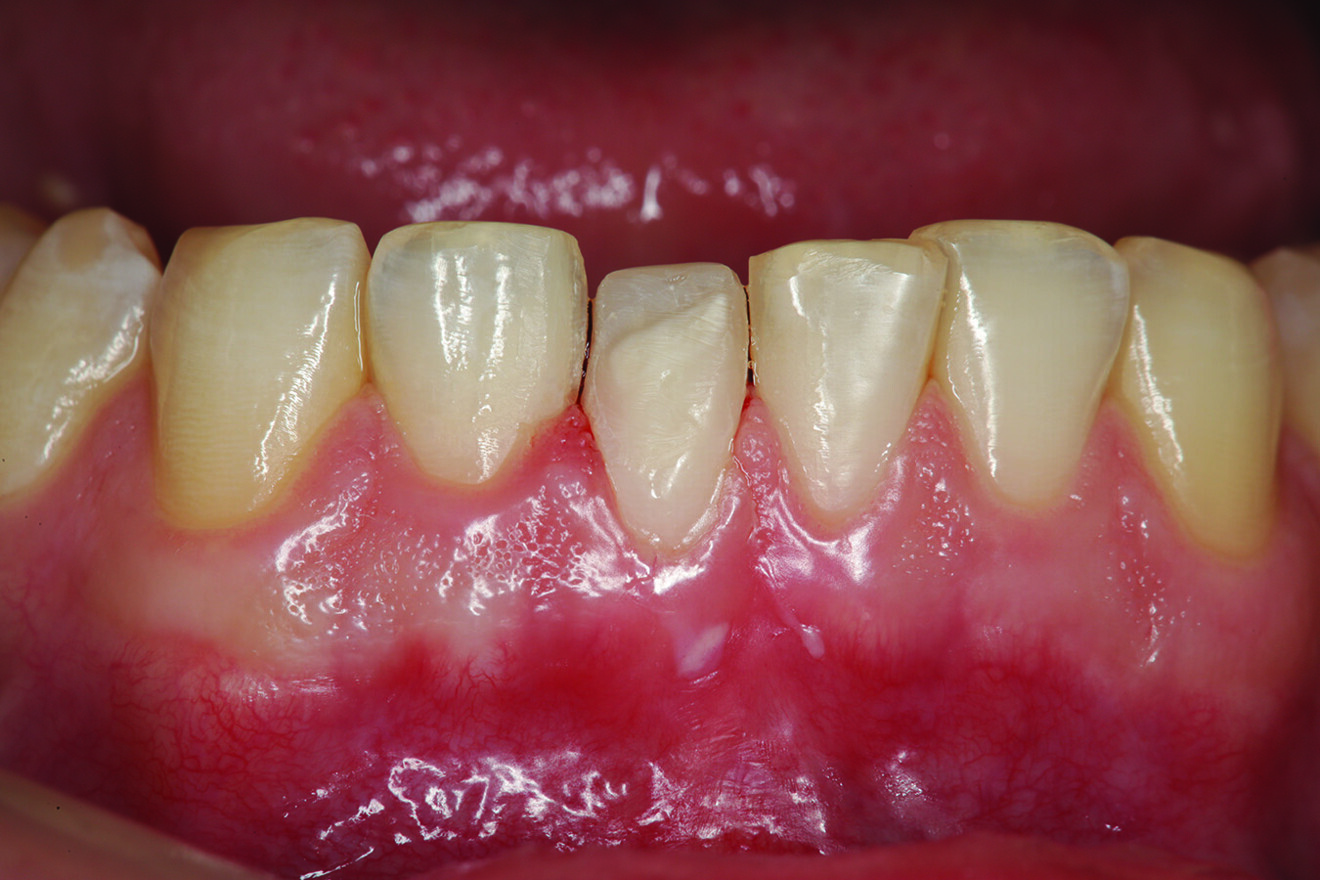

What about the alignment of the opposing teeth? It could be observed that excessive wear was present on the incisal edges of teeth #31 and 41 (Fig. 2). From the incisal view, exten­sive wear was seen on all mandibular inci­sal edges due to occlusal disease—which is often seen yet left untreated (Fig. 3). Tooth #41 was also facially positioned so that in pro­trusive excursion it engaged the palatal surface of tooth #11 prematurely, placing addi­tional stress on both the palatal surface and inci­sal edge of tooth #11 before coupling with the remainder of the maxillary anterior segment. This demonstrates that addressing these issues restoratively involves more than just fixing a chipped composite restoration.

Fig. 2: Teeth in protrusive excursion, showing excessive wear on the tooth (# 41) opposing tooth #11, indicating hyperfunction and increased functional stress on the restored area.